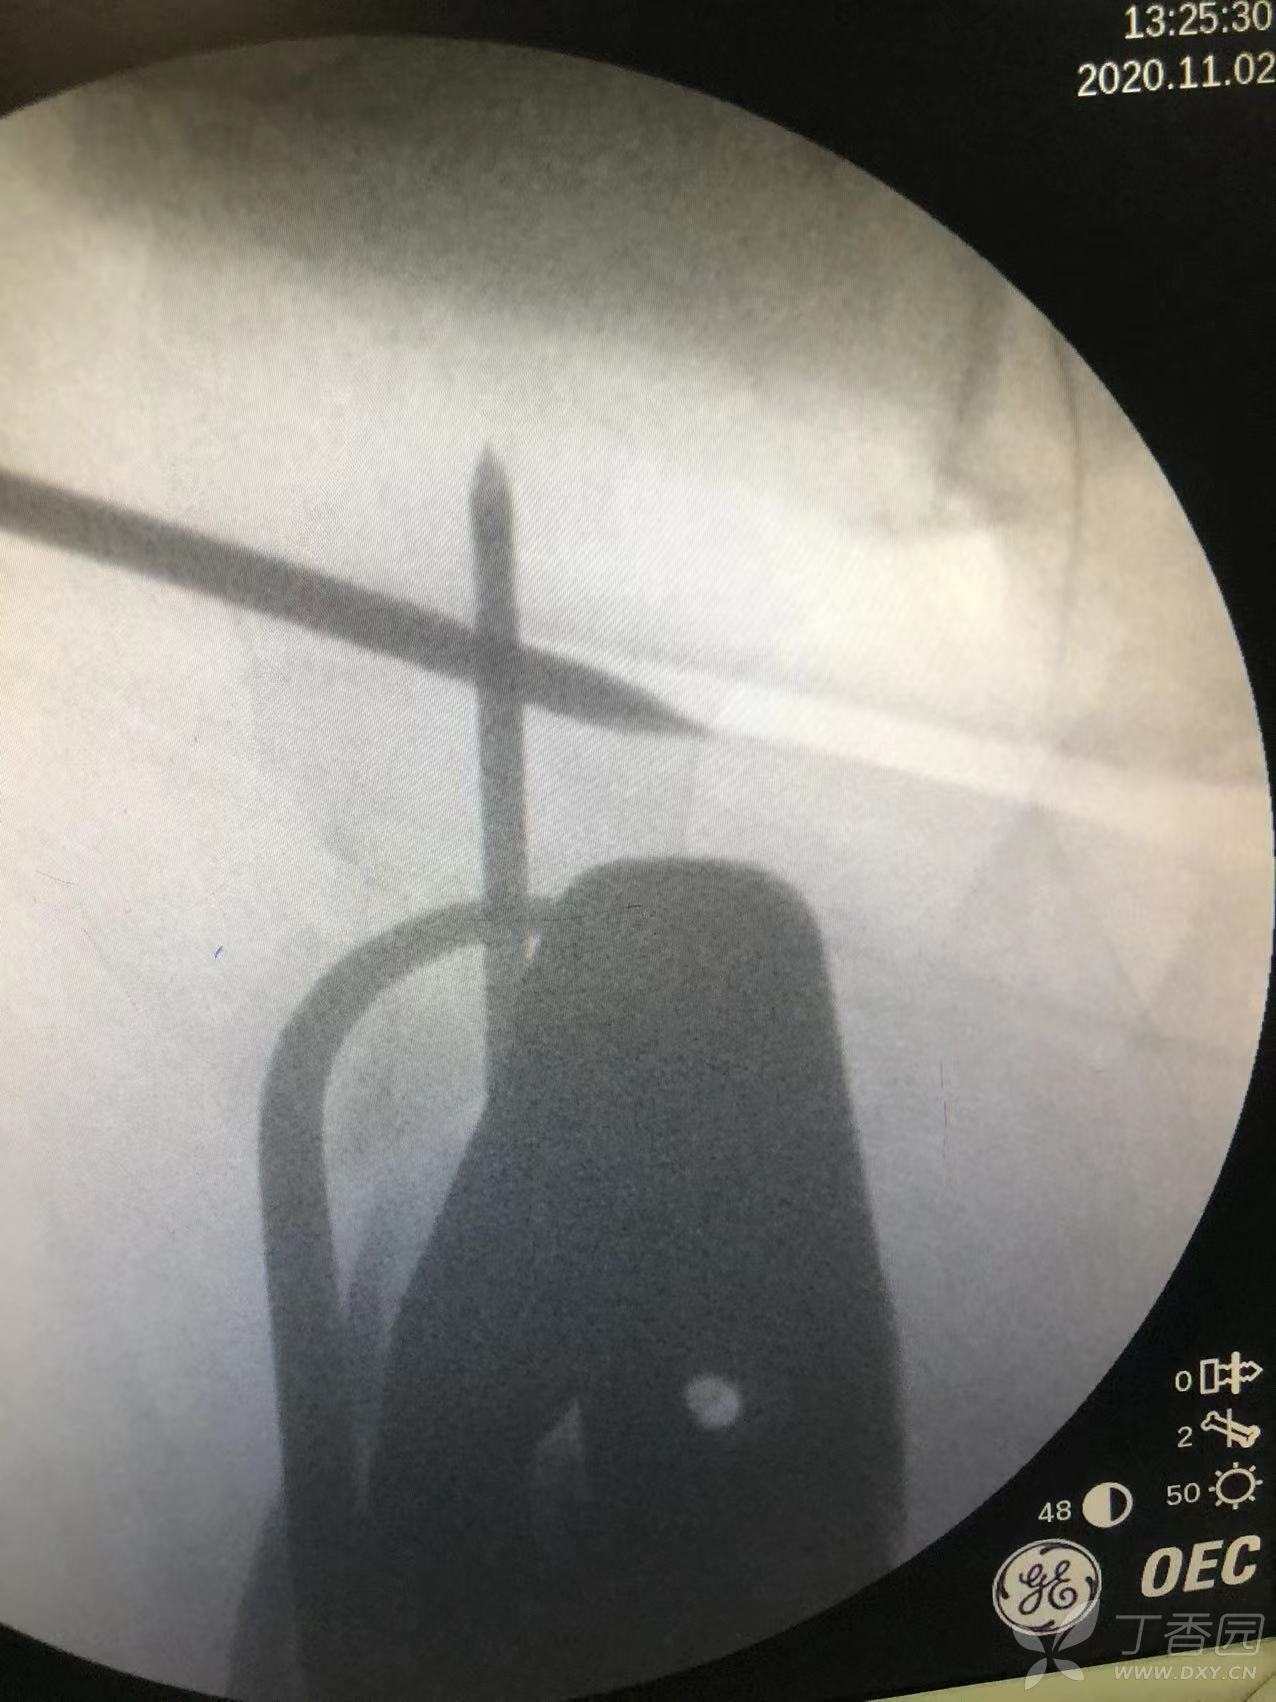

患者置于牵引床上,正位在股骨颈偏下方处垂直打入一枚4.0斯氏针。

通过这枚斯氏针控制近端旋转。

通过骨勾经头钉口经股骨前侧钩住小转子,见复位良好后打入主钉导针。